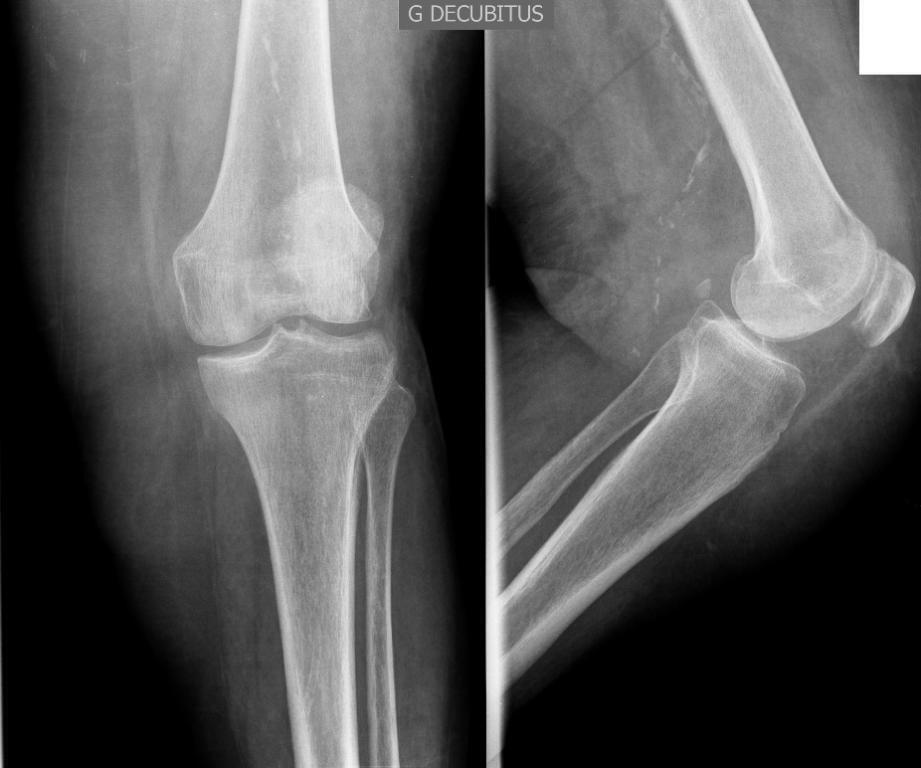

Le patient est hospitalisé. Des radiographies du genou gauche sont réalisées.

Figure 1.

Les radiographies sont normales (en dehors de calcifications artérielles), ce qui rend très peu probable une chondrocalcinose articulaire (un liseré calcique cartilagineux est présent dans la majorité des cas), le terrain ainsi que la topographie étant par ailleurs peu typiques. La goutte reste le plus probable et peut donner des atteintes d’allure pseudo-septique très inflammatoires. On ne peut éliminer une arthrite septique avant le résultat de la culture, le germe ayant pu être manqué à l’examen direct.